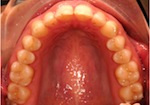

vorher

nachher

Patientin – 29 Jahre, Angle Kl. I, Invisalign für 9,5 Monate

Persistierender 52

(hier bereits entfernt)

12 war distal von 52 durchgebrochen